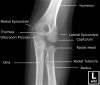

5. Approach to the Elbow X-ray

Examine fat pad(Soft tissue)

(1) Fat pad sign does not equal fracture

(2) Fat pad sign does indicate in increased chance of a fracture

Examine the radiographic lines(Alignment)

Examine the individual bones(Bone & Cartilage)

-> On each of the views of the elbow, individual bones should be carefully examined for fracture which appear as cortical disruption or linear lucencies.